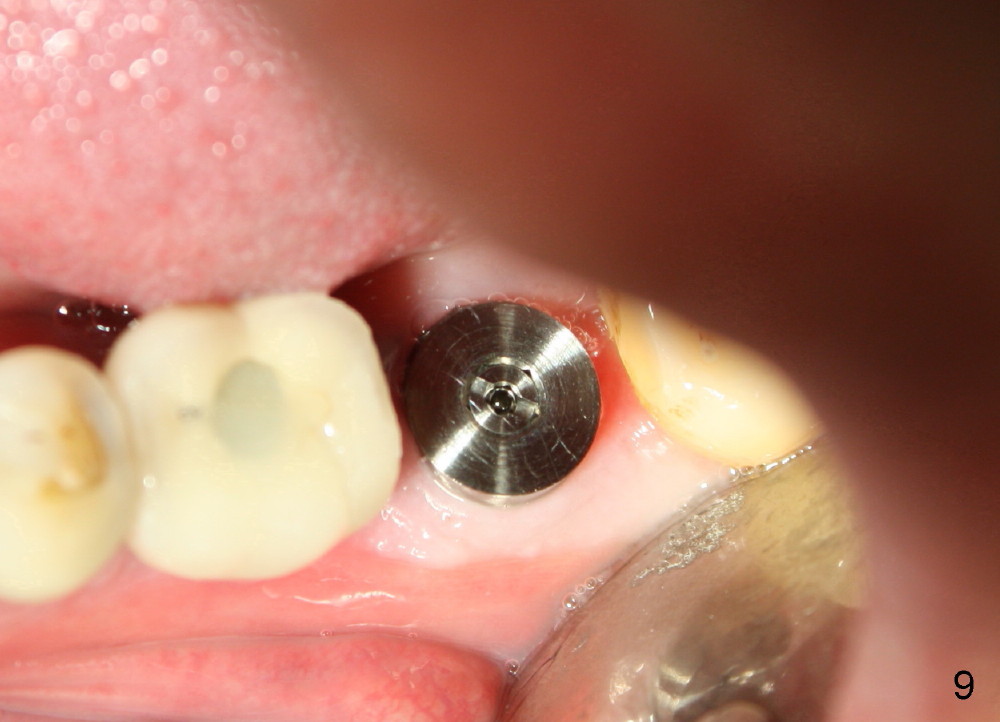

The septum of the socket is thin (Fig.3*), and easily removed, leaving a large socket. Osteotomy is initiated with 2 mm pilot drill in the middle of the socket, slightly mesiolingual, since the buccal and distal bone is low and defective. Reamers (2.5 to 4 mm in diameter) are sequentially used to enlarge osteotomy and harvest autogenous bone (Fig.4 (3 mm reamer in place). When 5 mm tap is placed, there is no stability. Six mm tap gains some stability, but the socket is not closed. Seven mm tap achieves strong stability and is closing the socket (Fig.5). Ultimately a 7x14 mm implant is placed with insertion torque more than 60 Ncm (Fig.6). The implant almost obliterates the socket (Fig.7). The harvested autogenous bone is placed in the buccal and distal aspects of the socket before Chromic gut suture (4-0) is placed distally. Fig.8,9 show the healing socket 6 days and 1.5 months postop, respectively. Osteointegration appears to occur in 2.5 months (Fig.10, compare to Fig.6). Bone level remains the same 1 year post cementation (Fig.11).